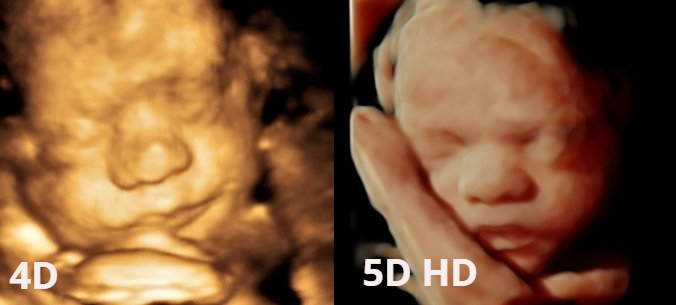

Resumiendo y en pocas palabras, 3D y 4D son los mismos tonos y misma calidad de imagen sin embargo con el 4D se podía visualizar al bebé en tiempo real.Aparición ecografía 5D

Con la tecnología 5D sí se ha producido un importante salto de calidad y nitidez de la imagen y sensación de realismo, pues es posible visualizar al bebé con una textura muy parecida al tono de la piel y el hecho de poder modificar el punto de luz durante la visualización hace que gane en una mayor sensación de realismo y profundidad.

o lo que algunos ya llamán 6D, que es una imágen mejorada del 5D.